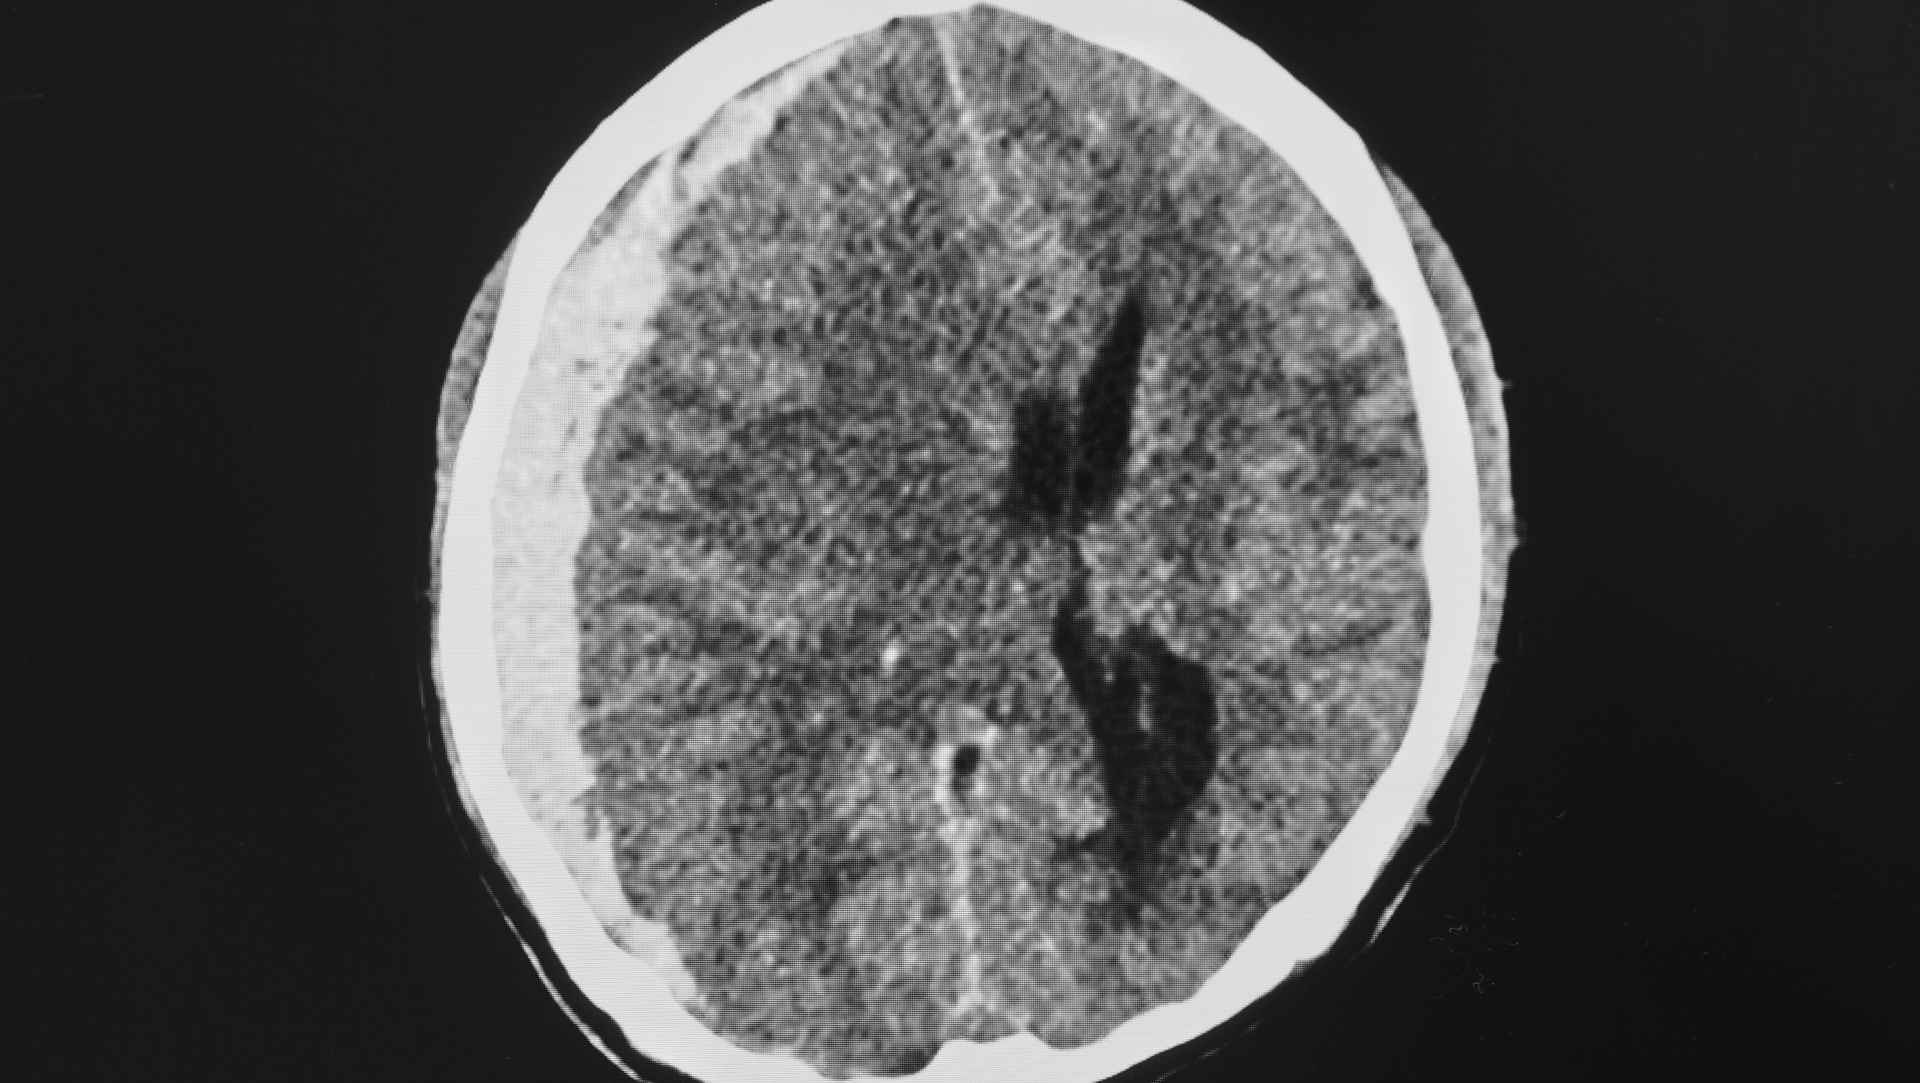

- Invasive intracranial pressure (ICP) monitoring had become a de facto standard in many ICUs for severe traumatic brain injury (TBI), embedded in practice pathways and guideline recommendations, despite limited randomised evidence.

- Globally, access to ICP monitors is variable; the trialists sought evidence relevant to both high-resource and resource-limited environments where clinicians rely on neurological examination and CT imaging.

- Does protocolised management guided by invasive ICP monitoring improve patient-centred outcomes compared with protocolised management guided by serial imaging and clinical examination in severe TBI?

- Imaging–clinical examination strategy (Imaging–Clinical Examination Group): tiered management driven by scheduled/triggered CT imaging and neurological examination (including deterioration signals and radiological signs of raised ICP), without continuous ICP data.